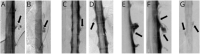

Results: Among 398 patients with SIH and extradural CSF on spinal imaging, multiplicity of CSF leaks was observed in none of 291 patients with type 1a ventral leaks and in 4 (6.2%) of 65 patients with type 1b (postero-) lateral leaks. Among 97 patients with SIH from spinal CSF-venous fistulas (type 3 leaks) who did not have extradural CSF on spinal imaging, 9 patients (9.3%) had multiple fistulas (p < 0.0001 for comparison between groups). Type 3 and type 1a or 1b CSF leaks coexisted in an additional 5 patients.